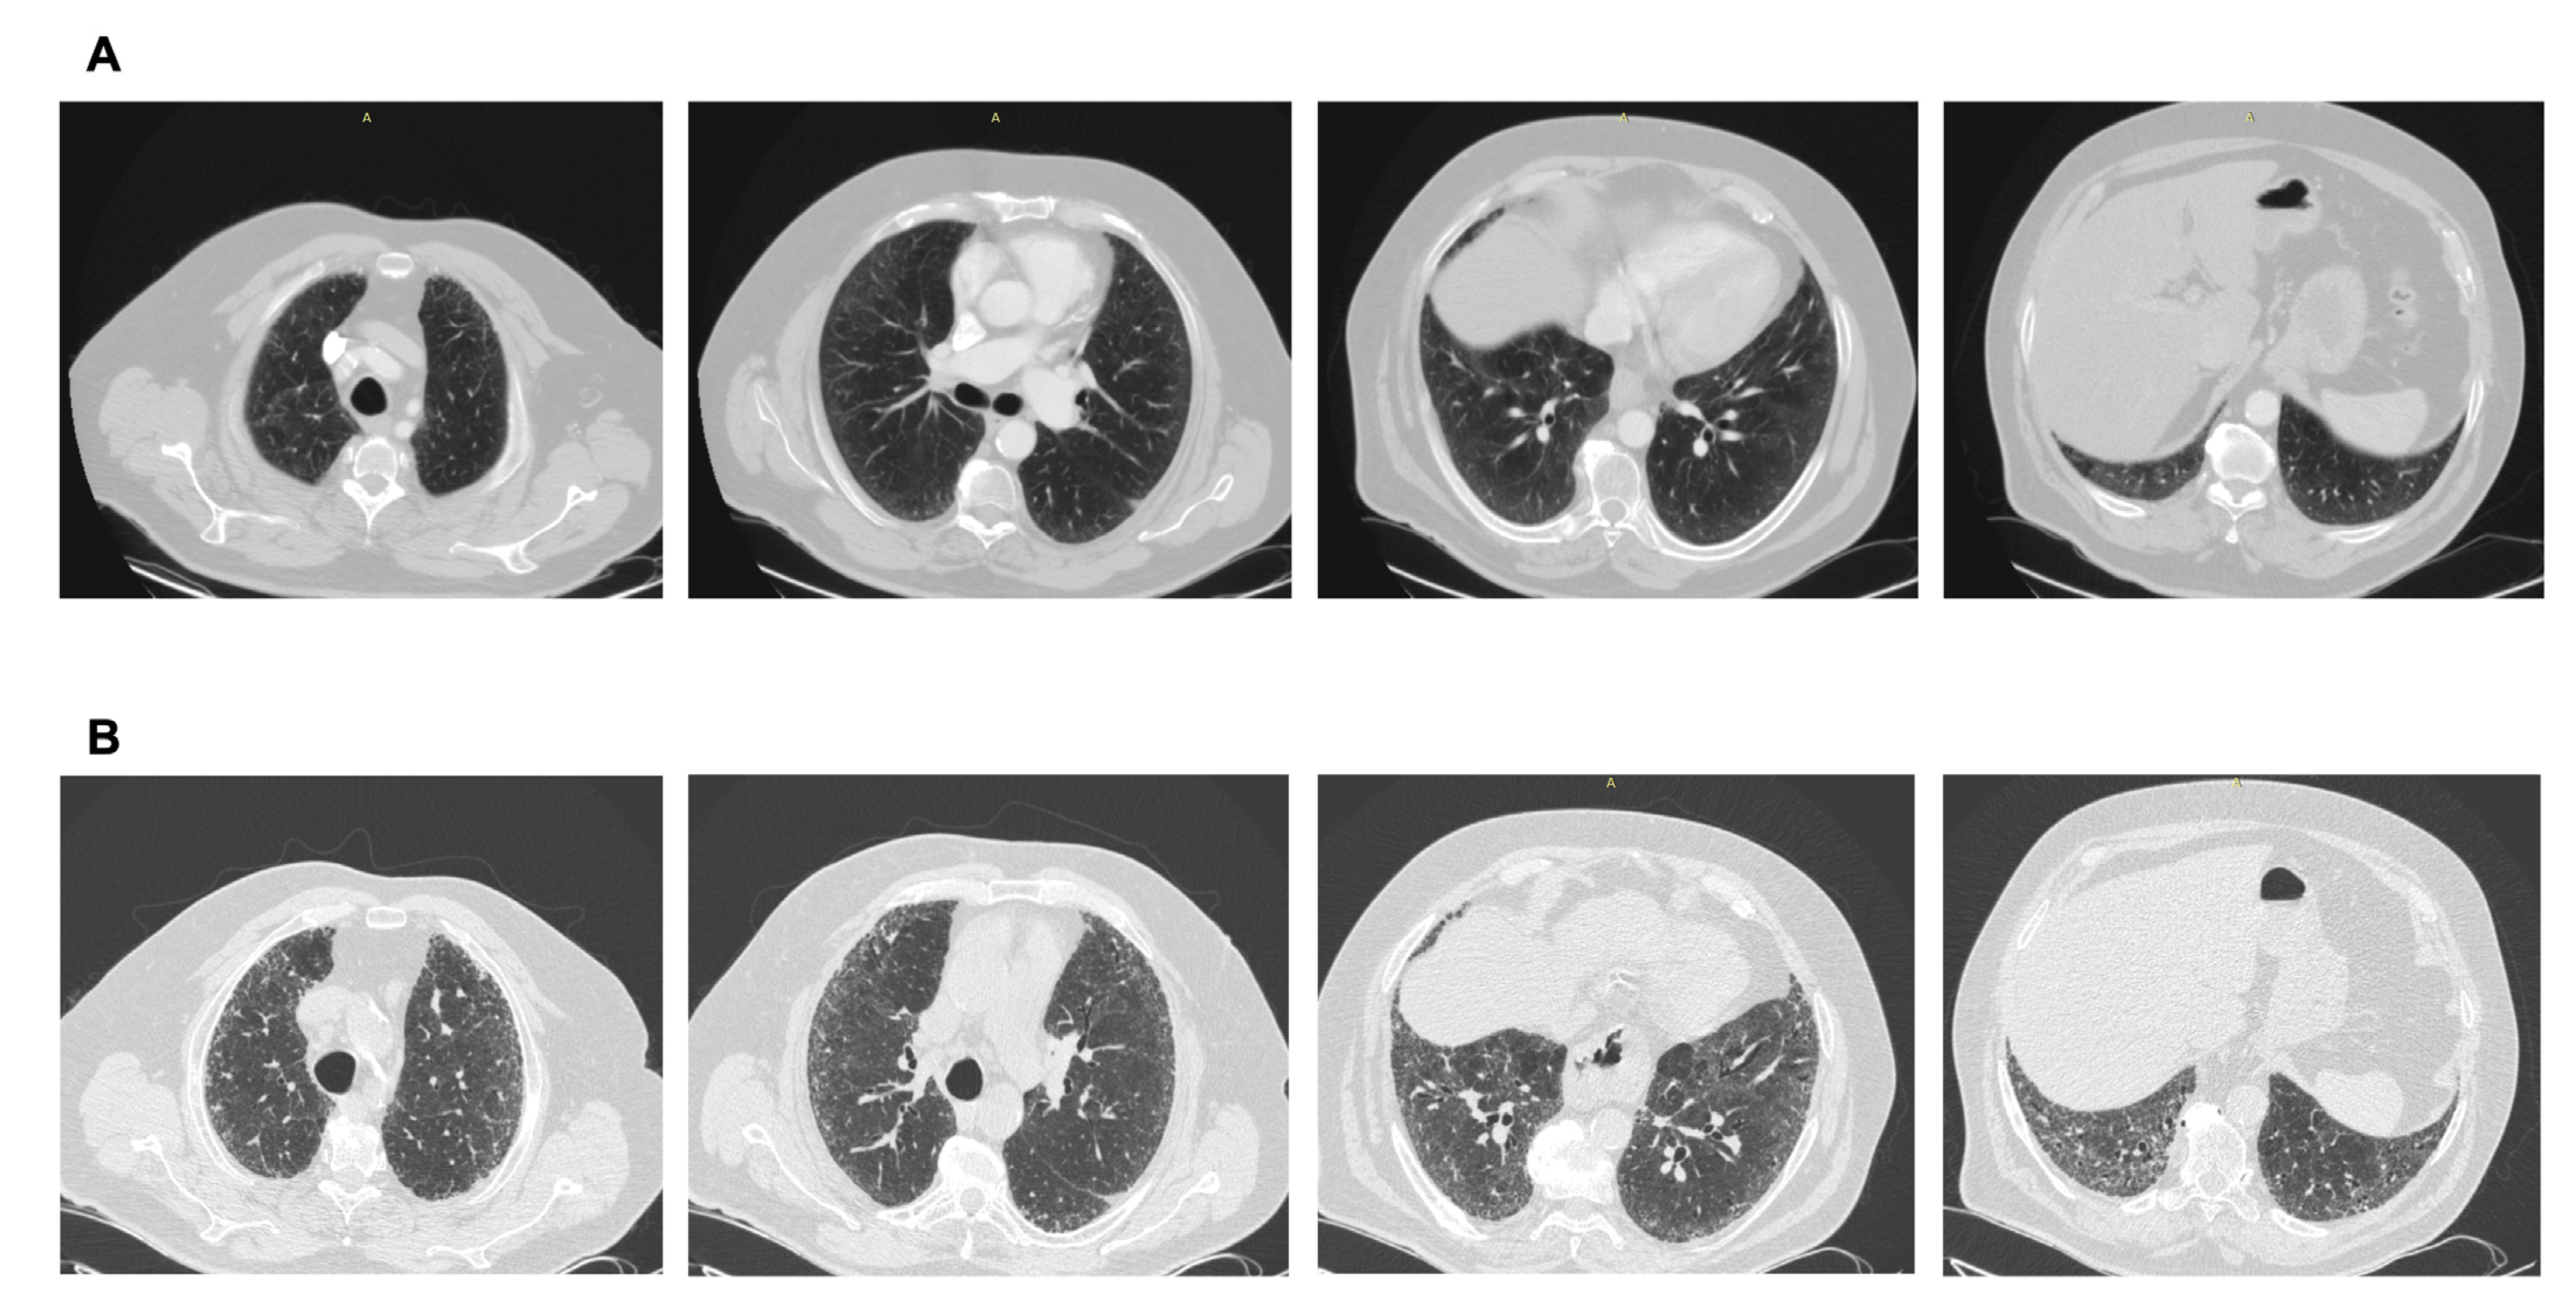

2.2. ILA Subcategorization

- Non-subpleural ILAs: ground-glass opacity and reticular opacities without a predominant subpleural localization.

- Subpleural nonfibrotic ILAs: ground glass opacity and reticular opacities with a predominant subpleural localization and without evidence of fibrosis.

- Subpleural fibrotic ILAs: with a predominant subpleural localization and with evidence of pulmonary fibrosis (traction bronchiectasis, architectural distortion, and honeycombing).